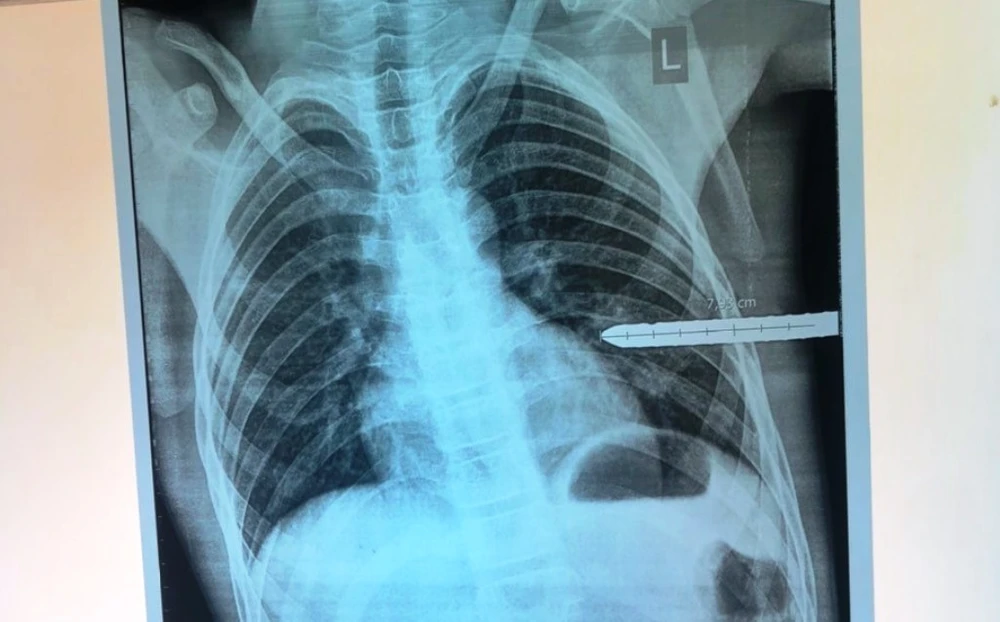

Hình ảnh chụp cho thấy thanh sắt đâm vào phổi em Đ. Ảnh: BV Sản nhi Nghệ An.

Ngay khi tiếp nhận, BV Sản nhi Nghệ An đã xét nghiệm, chụp X-quang, siêu âm…và chuyển bệnh nhi từ phòng cấp cứu lên phòng mổ.